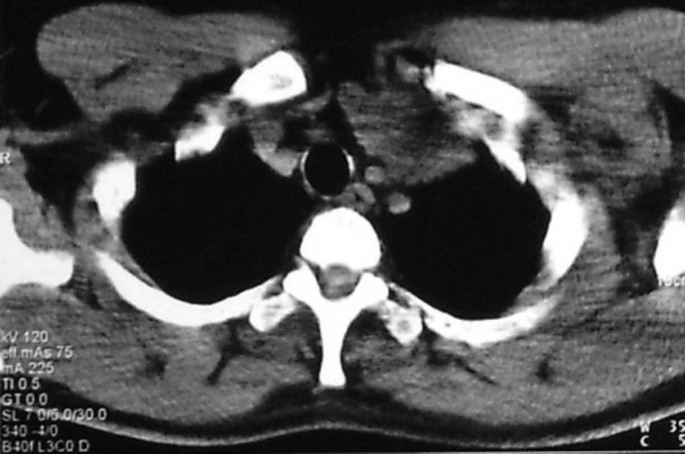

Рентгеновские снимки тератомы средостения: Диагностика и лечение

Раздел: Фотоэссе